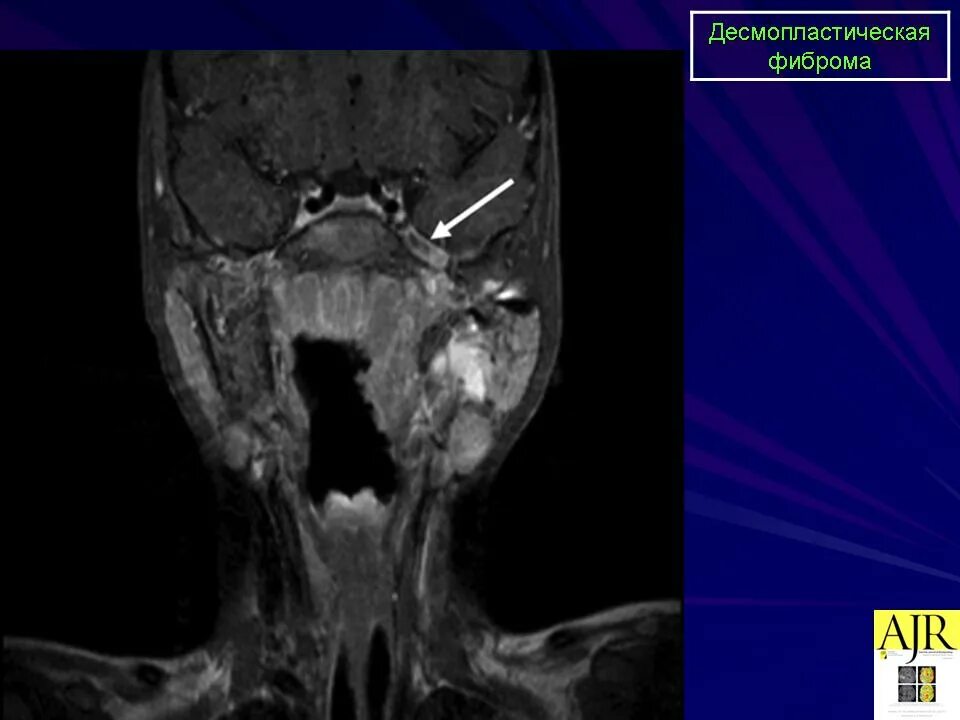

Фиброма кт